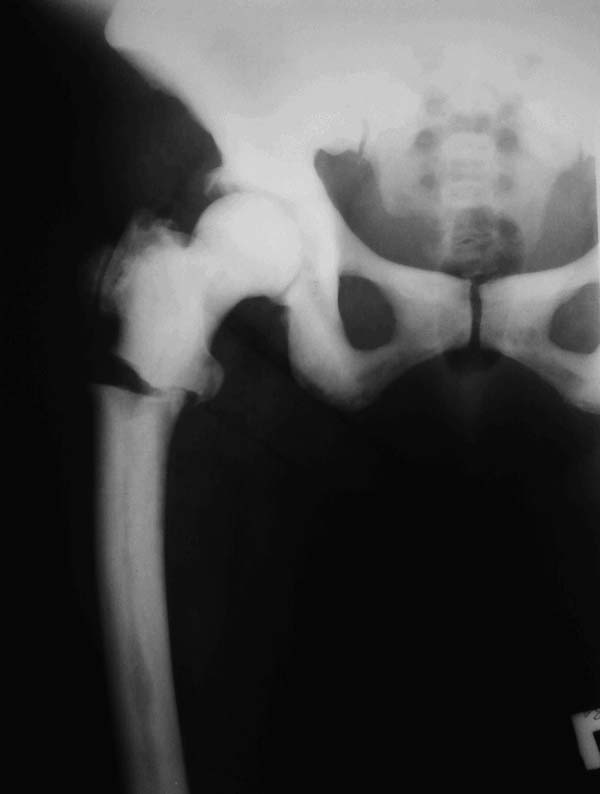

У нас есть пациентка с мраморной болезнью (остеопетроз - выявлен в детстве). К нам попала с рентгенологической картиной патологического подвертельного перелома правой бедренной кости. Из анамнеза - около 1,5 месяца назад появилась ноющая боль в области правого тазобедренного сустава, периодически усиливающаяся, находилась на лечении в ревматологическом отделении (родственники), с эффектом, боли в большей степени купировались, самостоятельно ходила, приступая на правую ногу; однако при транспортировки пациентки домой, а именно выхода из машины почувствовала резкую боль в правом тазобедренном сустава, СМП доставлена в нашу клинику. Пациентка была, обследована и подготовлена на операцию. 3 дня назад производилась: закрытая репозиция и попытка интрамедуллярного остеосинтеза PFN Long Zimmer, однако удалось рассверлить лишь канал в проксимальном отломке бедренной кости (частичный раскол), дистальный отломок не поддавался расверливанию, многократные попытки, разными сверлами, разного диаметра (канал просто отсутствует, монолитная кость). На накостный остеосинтез решено было не переходить. Так и завершилась операция. После операции попытки наложения скелетного вытяжения за бугристость большеберцовой кости тоже неудачны. Нужен совет: 1. Стоит ли вообще еще пытаться оперировать, синтезировать? 2. Если стоит, то каким фиксатором лучше сделать?